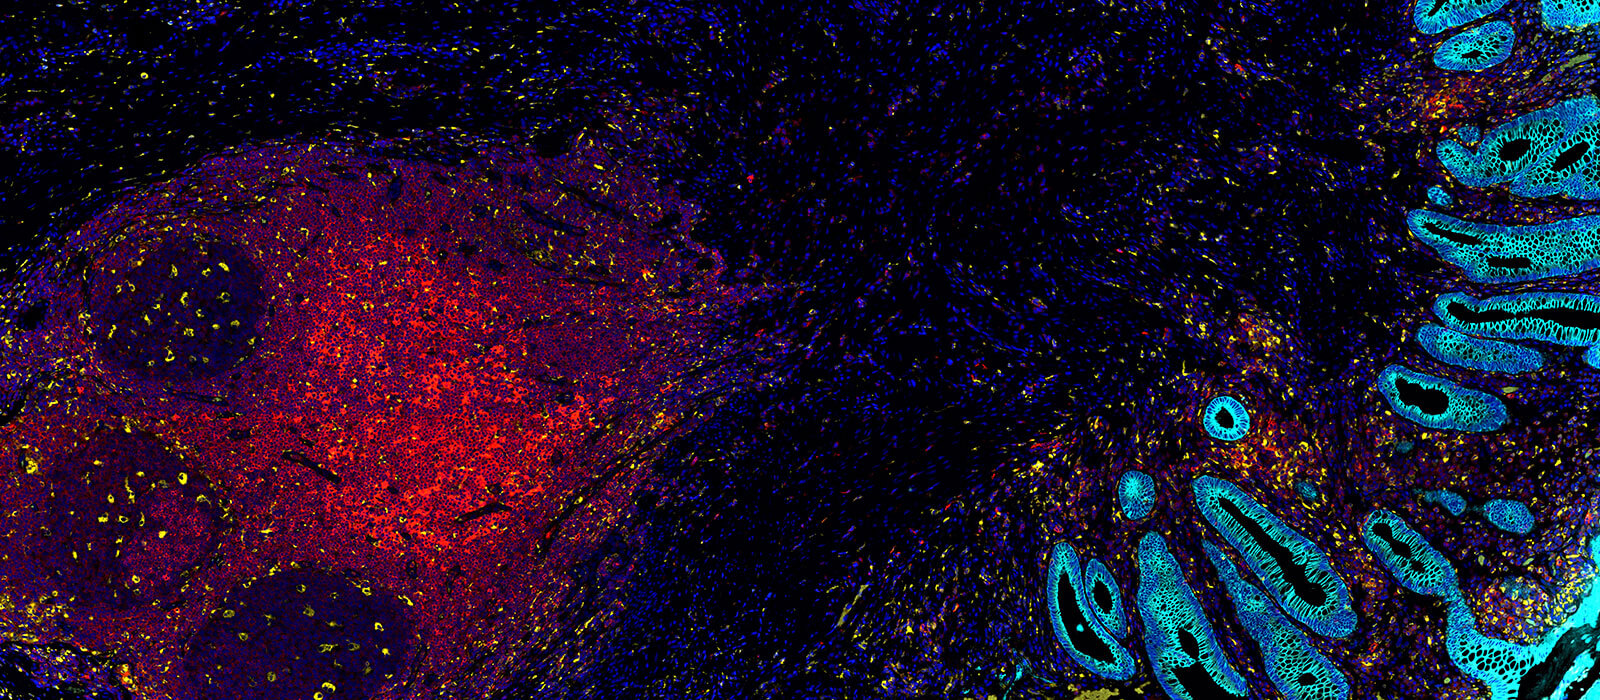

This is excellent news for Owkin’s recently launched MOSAIC initiative. MOSAIC is Owkin’s landmark $50 million project to revolutionize cancer research through the use of spatial omics, a set of cutting-edge technologies that offer unprecedented information on the structure of tumors. By generating and analyzing unprecedented amounts of spatial omics data in combination with multimodal patient data and artificial intelligence, MOSAIC aims to unlock the next wave of treatments for some of the most difficult-to-treat cancers. Collaborating with Gustave Roussy, the University of Pittsburgh through the UPMC Hillman Cancer Center, Lausanne University Hospital, Uniklinikum Erlangen/Friedrich-Alexander- Universität Erlangen-Nürnberg, Charité - Universitätsmedizin Berlin, and providers of analytical instrumentation and assays for spatial biology. MOSAIC will use 7,000 tumor samples from patients, making it over 100 times larger than any existing spatial omics datasets. Owkin and the MOSAIC partners will mine this resource for immune-oncology disease subtypes in pursuit of biomarkers and novel therapies.